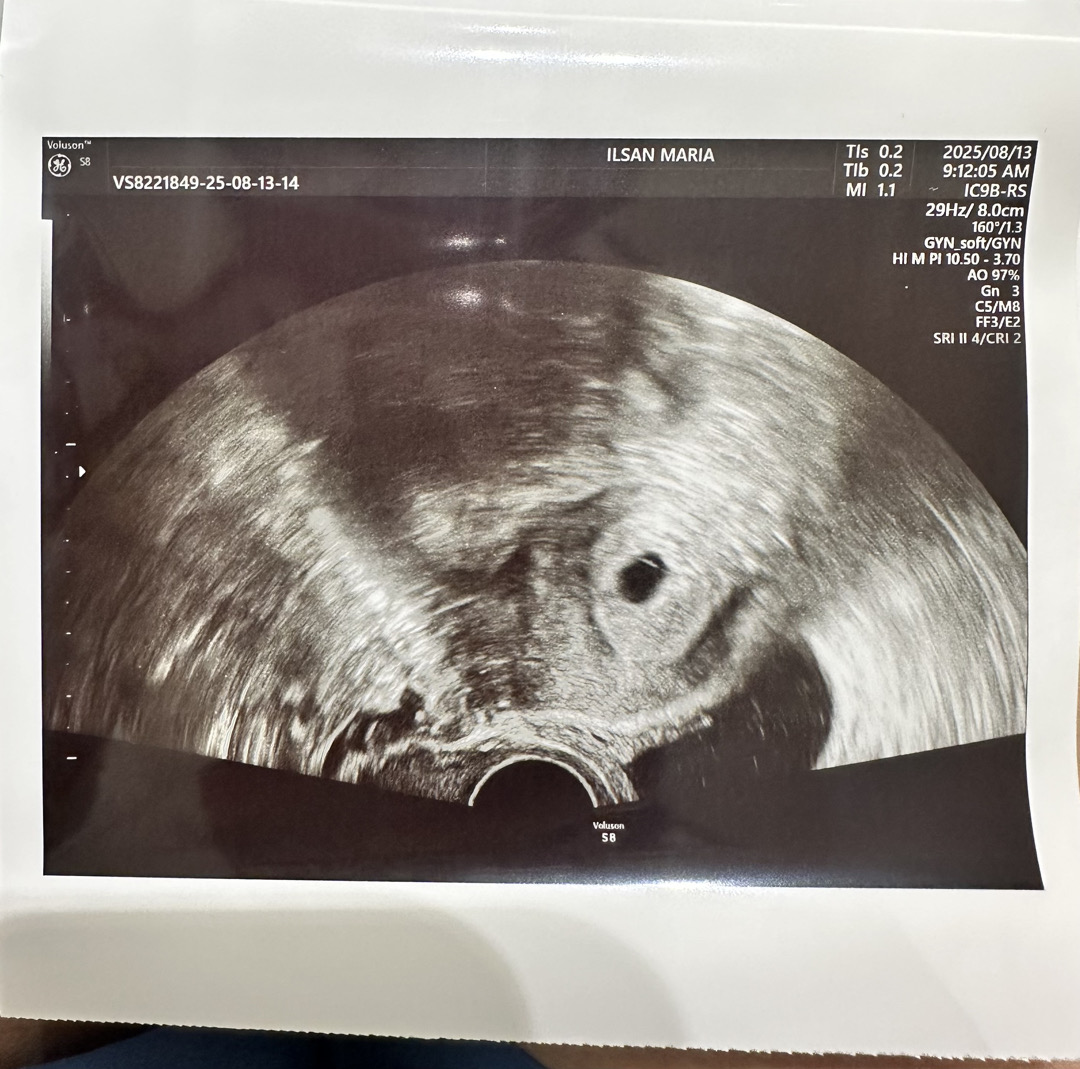

5주0일 초음파 처음 봤는데요!

안녕하세요! 5주0일차고 오늘 초음파 처음봤어요 아기집이 0.7cm라고 하시더라구요! 아직 난황은 안보이더라구요 근데 아기집 윗쪽에 가느다랗게 흰색 선이있는데 그게 난황이 만들어지고 있는걸까요?? 집와서 자세히보고 안거라서 선생님께 못여쭤봤거든요 ㅠ